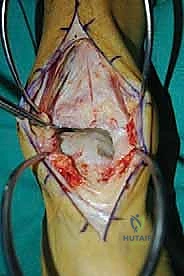

الغوص العميق في جراحة الطعم الخيفي الهيكلي (Structural Allograft Reconstruction)

يهدف هذا الإجراء العبقري إلى استبدال الغضروف والعظم التالفين والميتين بنسيج سليم تماماً مأخوذ من متبرع متوفى (طعم خيفي - Allograft). هذا الطعم يتم تعقيمه وحفظه في بنوك الأنسجة العالمية وفقاً لأعلى المعايير الطبية الصارمة لضمان خلوه من أي أمراض معدية والحفاظ على حيوية الخلايا الغضروفية.

- الترميم التشريحي الحقيقي: يسمح باستعادة الشكل الهندسي الدقيق لعظم الكاحل، بما في ذلك المنحنيات المعقدة لكتف التالوس.

- توفير غضروف طبيعي (Hyaline Cartilage): الغضروف المزروع هو غضروف زجاجي طبيعي،